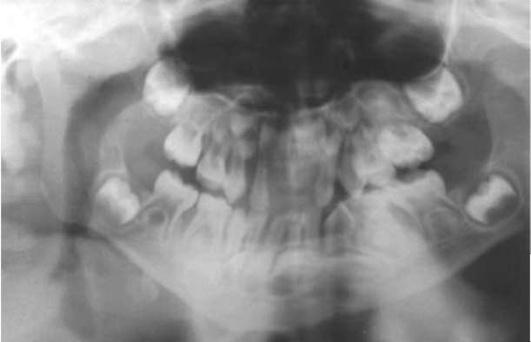

У детей в период полового созревания агрессивный периодонтит (ювенильный пародонтит) проявляется избирательным поражением первых моляров и центральных резцов. Заболевание возникает у детей 10-13 лет и характеризуется интенсивным поражением пародонта, быстро прогрессирующей деструкцией костной ткани, небольшим количеством наддесневого и поддесневого налета и зубного камня, незначительным воспалением десны. Генерализованная форма заболевания встречается редко (рис. 31-10), однако возможен переход локализованной формы в генерализованную, особенно без лечения. В течение 1-2 лет заболевание приводит к почти полной потере удерживающего аппарата пораженных зубов. Патологический процесс протекает с частыми обострениями (2-4 раза в год) и короткими ремиссиями. В период обострения появляются выраженная гиперемия и отечность десны, подвижность зубов, обильная экссудация, пародонтальные карманы достигают 8-14 мм. Клиническая ситуация осложняется потерей отдельных зубов, нарушением окклюзии, подвижностью зубов, дисфункцией височно-нижнечелюстного сустава. Рентгенологически диагностируются чашеобразные очаги деструкции альвеолярных отростков в области резцов и моляров (рис. 31-11).

pic 0212

Рис. 31-11. Ортопантомограмма при ювенильном пародонтите.